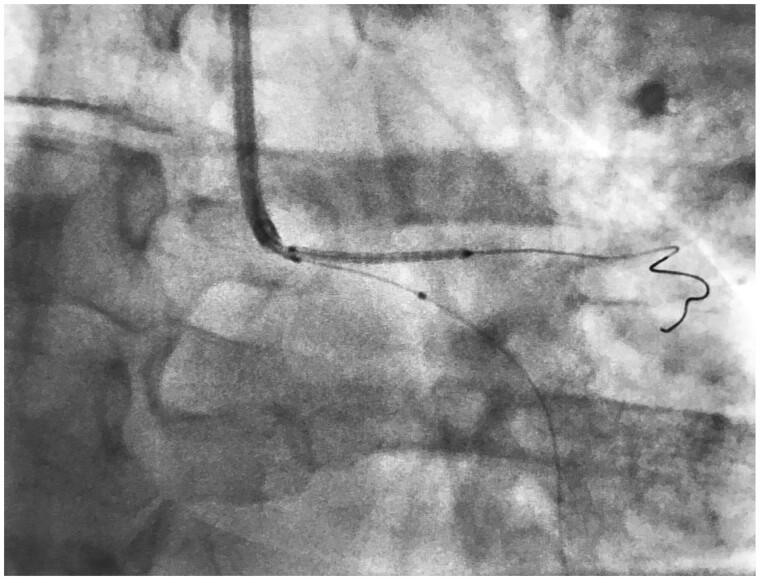

Simultaneous intravascular ultrasound for precise ostial stent placement.